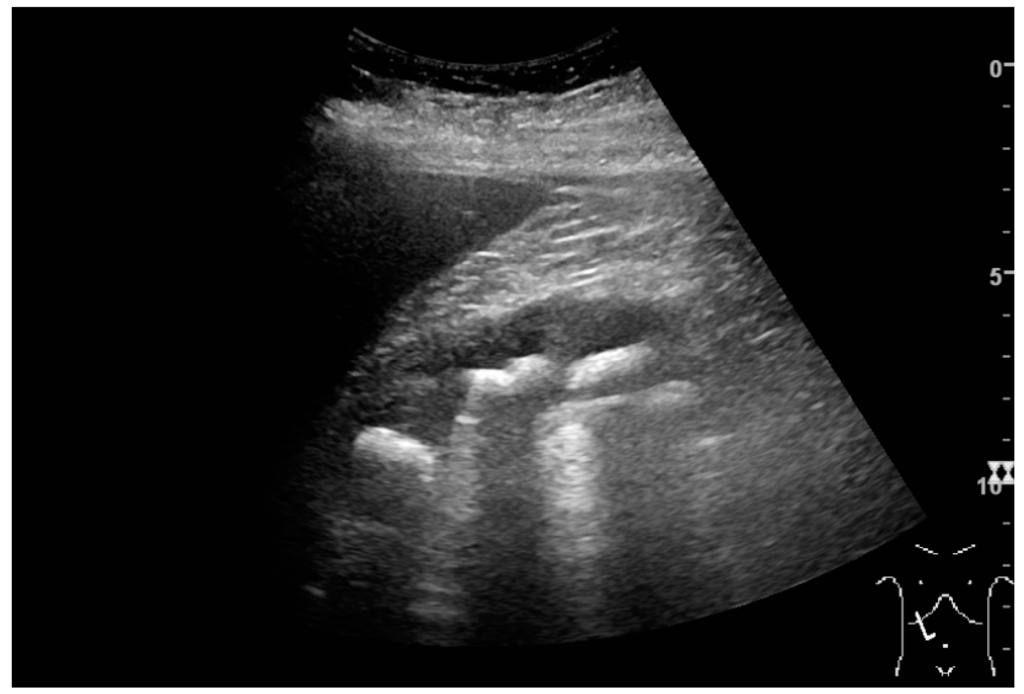

Figure 20. Staghorn calculi filling the entire collecting system and creating pronounced shadowing.